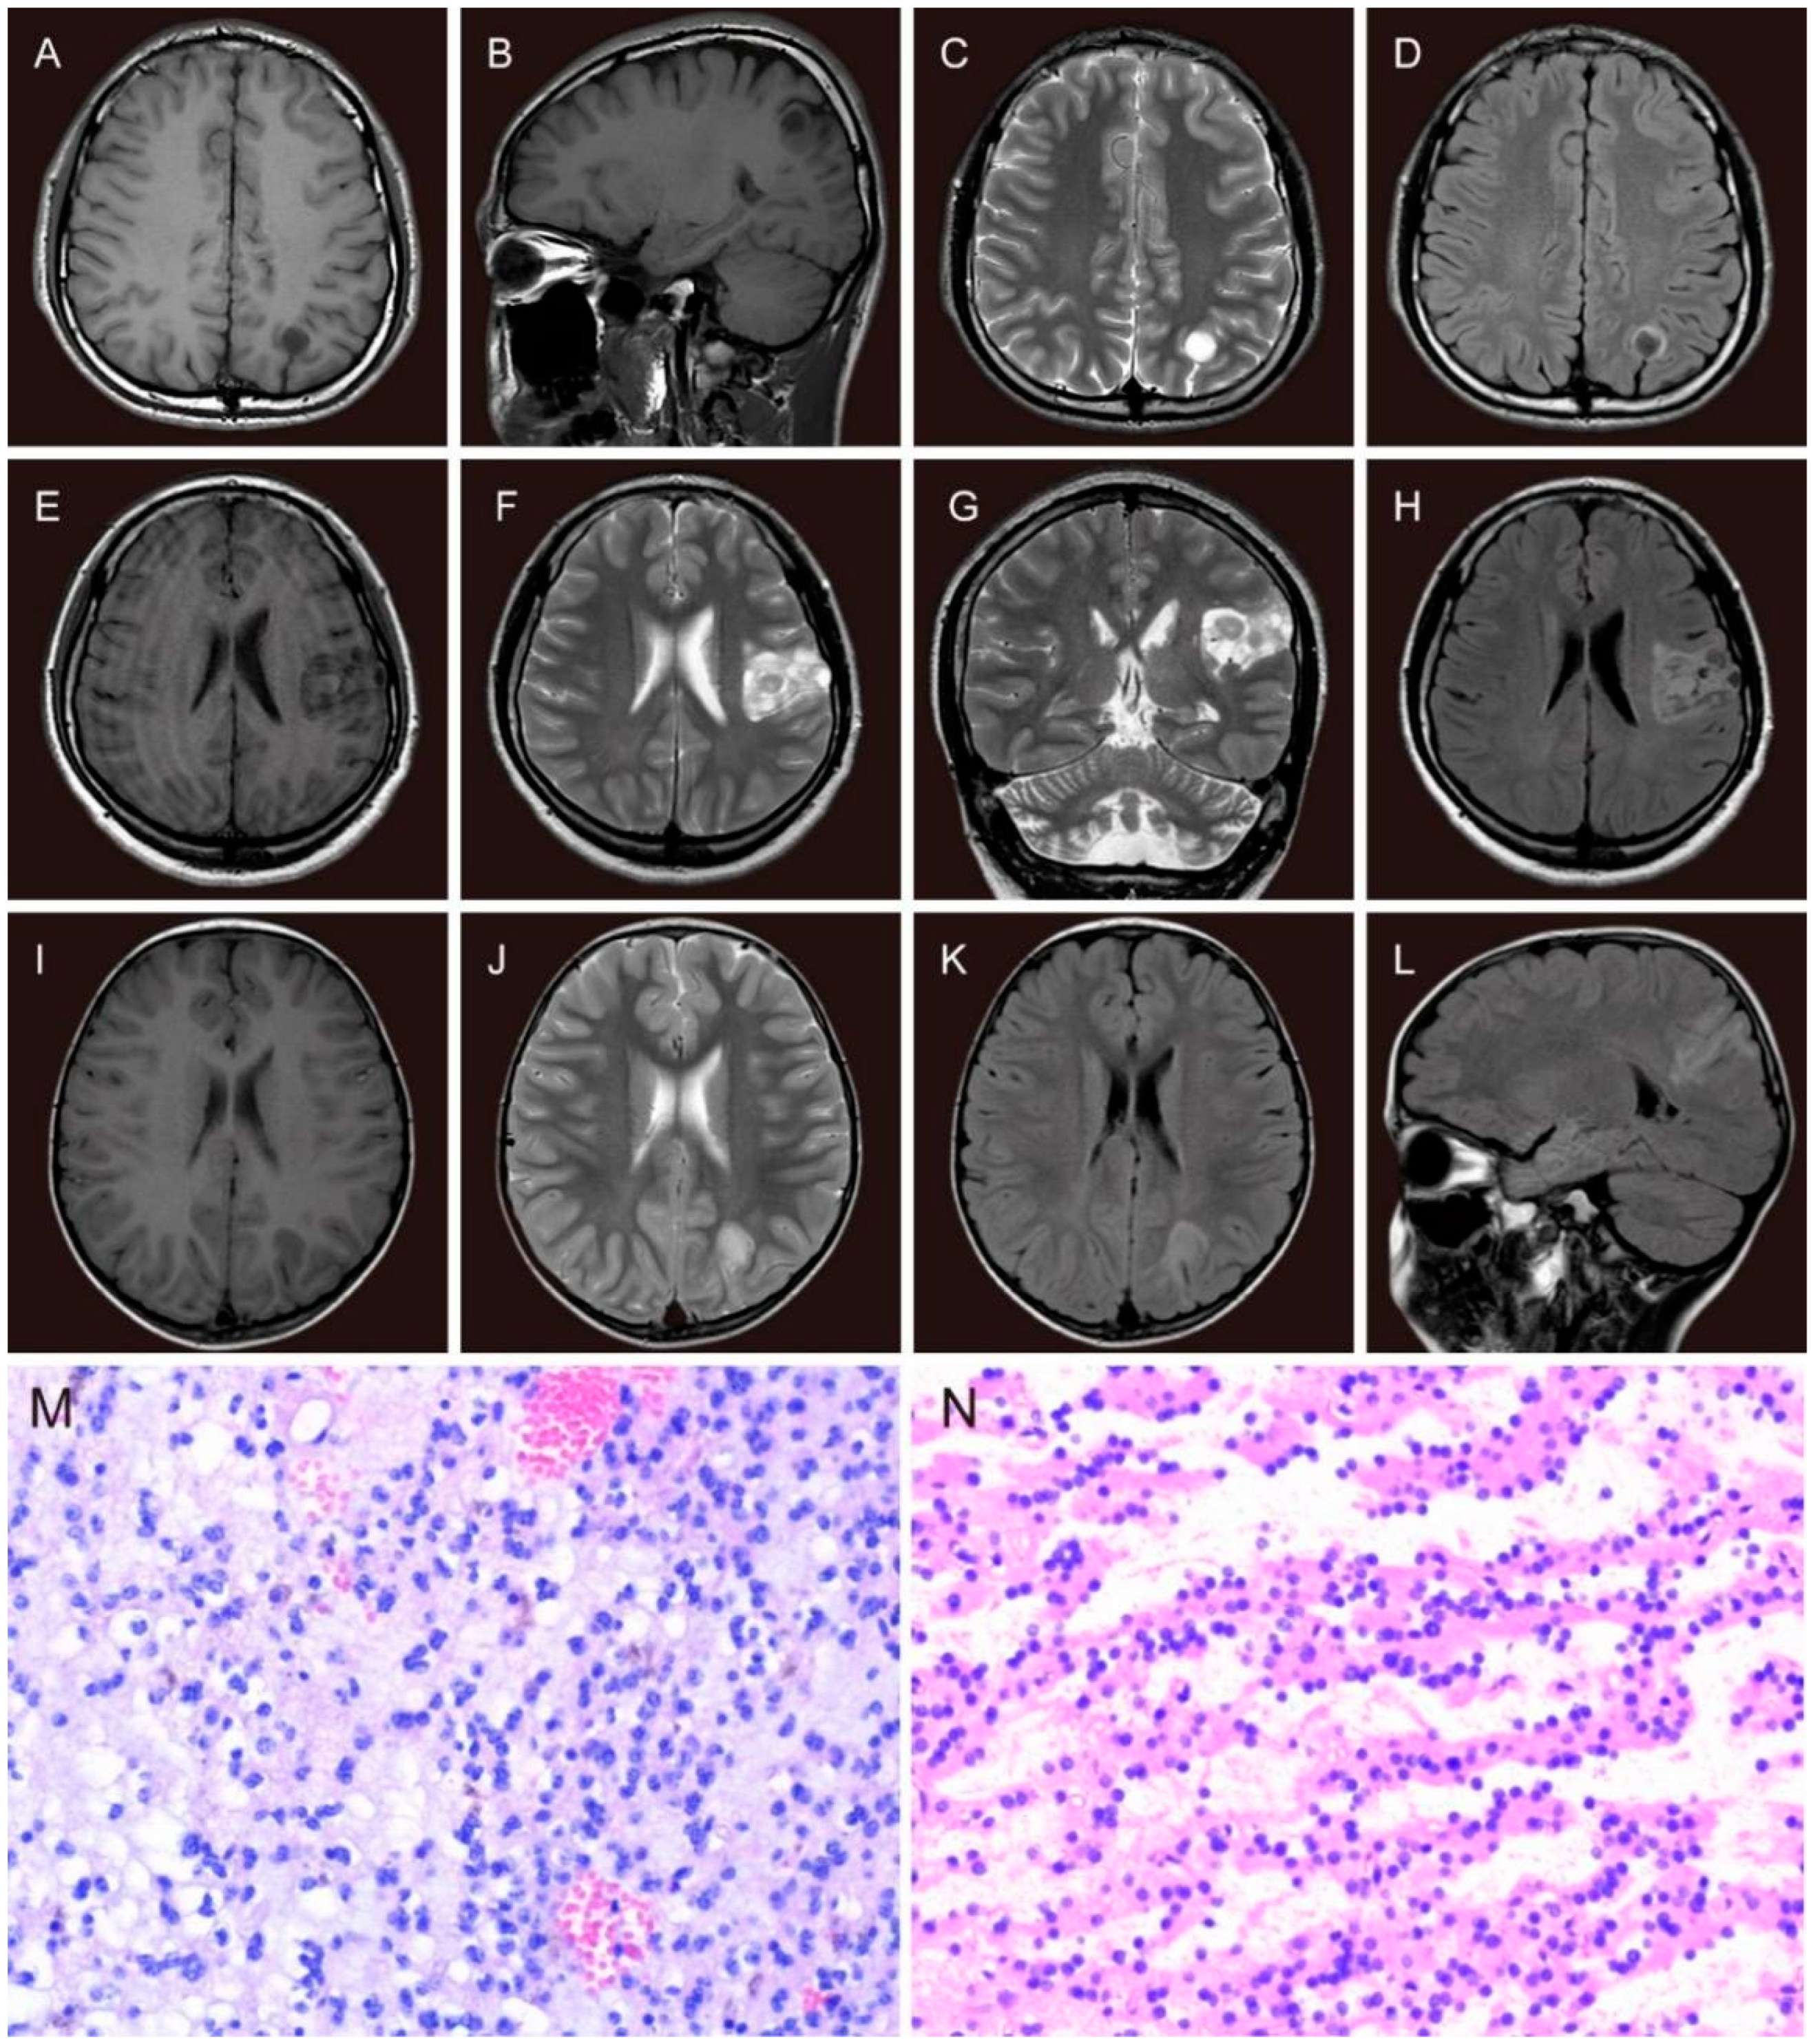

Preoperative non-invasive examinations include seizure semiology, detailed medical history, neurological examinations, magnetic resonance imaging (MRI), and long-term scalp video-electroencephalogram (VEEG). Seizure types were evaluated by experienced neurosurgeons and neurologists based on the International League Against Epilepsy (ILAE) classification of epilepsies [21,22]. All patients were scanned by MRI (1.5-T, Siemens, or 3.0-T, GE). MRI sequences were T1-weighted imaging, T2-weighted imaging, and fluid-attenuated inversion recovery (FLAIR). The tumor site, volume, and MRI subtypes (Figure 2A–L) were reviewed by a neuroradiologist. Tumor dimensions were measured with a digital ruler on MRI. The measurements were based on the abnormal signals on contrast-enhanced T1WI in high-grade tumors and T2WI in low-grade tumors. The tumor volume calculation was based on the formula for the normalized volume of an ellipsoid [23]. Tumors were classified as type 1 MRI (cystic-like or polycystic-like), type 2 MRI (nodular-like), or type 3 MRI (dysplastic-like) according to the classification presented by Chassoux et al. [11]. A standard 10–20 system of electrode placement with a 64 or 128-channel system was used for long-term video-EEG monitoring. Interictal epileptiform discharges (IEDs) were termed “regional” (only involved a single lobe or adjacent lobes), “unilateral” (involved the ipsilateral hemisphere of the lesion), and “bilateral” (involved both hemispheres). For patients whose seizures could be recorded, the ictal discharge patterns were classified as the same as the IEDs. The epileptogenic zone (EZ) was identified by electrophysiologists and neurologists according to the VEEG results and semiology.

Figure 2.

The MRI features and histopathological features of DNTs. The MRI features of type 1 (A–D): axial and sagittal slices, single cystic-like hypointensity on T1WI (A,B) and hyperintensity on T2WI (C), ring hyperintensity around the isointensity tumor with a clear gray-white matter boundary on FLAIR image (D); the MRI features of type 2 (E–H): axial and coronal slices, hypointensity on T1WI (E), hyperintensity on T2WI (F,G) and FLAIR image (H), all with a nodular-like iso-hypointensity; the MRI features of type 3 (dysplastic-like): axial and sagittal slices (I–L), slightly blurring of the gray-white matter demarcation with hypointense signal on axial T1WI (I), hyperintense signal on T2WI (J) and FLAIR images (K,L). Histopathological features of DNT (M,N): specific glioneuronal elements with a typical columnar structure composed of small oligodendrocytes and neurons floating within an interstitial fluid (H&E, ×200); (N): tumor cells were “striped” in loose areas of tumor tissue (H&E, ×200).

Surgery aimed to achieve tumoral resection as completely as possible without impairing normal function. Electrocorticography (ECoG) during the operation and other neuromonitoring facilities were performed to delineate the periphery of EZ and identify the functional areas. The extent of resection was defined according to the operative recordings, and postoperative MRI was performed within 48 h. The extent of resection was defined as “gross total resection (GTR)” with no contrast-enhancement on T1WI in high-grade tumors and hyperintensity on T2WI in low-grade tumors [23], “near-total resection (NTR)” with less than 10% of the initial tumor volume, and “subtotal resection (STR)” involved more than 10% of the tumor remnant. For tumors located in the anterior or medial temporal lobe, the standard anterior temporal lobectomy with or without medial structures was also defined as GTR. The pathological diagnosis of DNTs was confirmed by the neuropathologist. The typical features of DNT are specific glioneuronal elements with a typical columnar structure composed of small oligodendrocytes and neurons floating within an interstitial fluid (Figure 2M,N). Pathological features were divided into three subtypes confirmed by the pathologist. The simple form was composed of a specific glioneuronal element. The complex form consisted of specific glioneuronal elements combined with glial nodules and focal cortical dysplasia (FCD). The nonspecific form consisted of glial and dysplastic components without specific glioneuronal elements and multinodular structure [12,24,25].